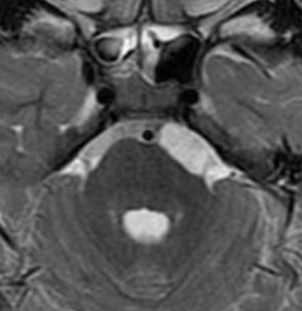

Субтенториальная эпидермоидная киста и арахноидальная киста полюса левой височной доли. КТ, аксиальный срез (а), МРТ, аксиальное Т2-ВИ (b) и аксиальное Т1-ВИ (с) после введения КС. Ни КТ, ни традиционные МР-изображения не позволяют четко дифференцировать эпиде моидные кисты от арахноидальных. Подобно кисте паутинной оболочки, эпидермоидная киста выглядит гиподенсной (а) или гиперинтенсивной (b) и гипоинтенсивной по отношению к паренхиме головного мозга (с) и не накапливает КС (с, стрелка). Однако МР-сигнал в эпидермоидной кисте неоднородный.